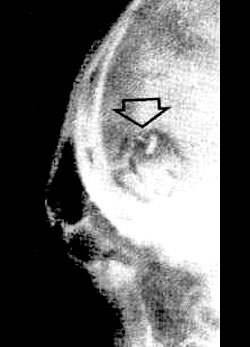

Pictured above left, is an X-ray of an object located in my skull

directly anterior to the frontal bone. The object was forcibly

implanted in 1967 at a hospital where I was awaiting an operation.

SÄPO had forced the surgeon to participate in their scheme,

preventing him from performing the original surgery.

A detail of one X-ray of my head shows

the nasal passages and the area behind the forehead. Two shaded

parts indicate the position of the transmitters that were surgically

removed at private hospitals overseas. One was inserted at Söder

Hospital, while another was the one I received in police custody in

1978. A third object on the X-ray is the first transmitter that the

police put in me on March 10, 1972, while a fourth was implanted

either at Stockholm’s detention center or in custody at Vasteras in

1973. The last transmitter shown in the X-ray was inserted under

sedation on November 26, 1975 at the Nacka Police custody center.

3. [implt3.jpg]:

Photo of x-ray showing another brain

implant in the skull of Robert Naeslund, 1987.

Detail:

"In this x-ray photograph taken the

day following the operation,

the 1/2cm deep area of branded